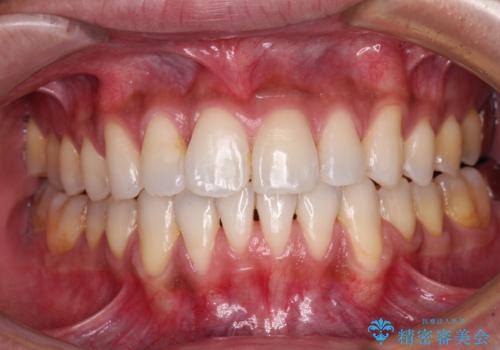

矯正歯科治療 → 叢生(でこぼこ・八重歯)

前歯のデコボコをインビザラインでスッキリと仕上げる

マウスピース矯正で前歯のガタつきを改善

上下前歯のデコボコをきれいに インビザラインによる矯正治療